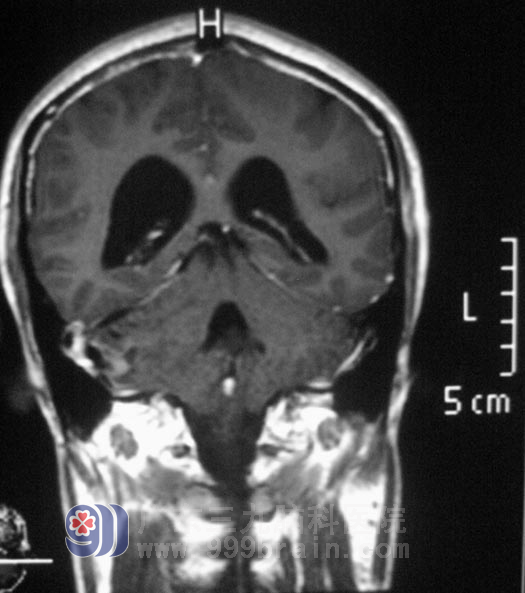

广东三九脑科医院头颅MR检查提示:右侧小脑半球占位性病变,脑积水形成,考虑血管母细胞瘤可能。

完善相关检查后,由综合神经外科 鲁明主任主刀,在全麻下行右侧小脑半球血管母细胞瘤切除术,术中见局部脑组织呈灰白色、肿胀,切开脑皮质,有囊性变,囊液呈淡黄色,显微镜下见肿瘤呈粉红色,血管丰富,在显微镜下予肿瘤全切。手术后的周先生头痛头晕症状明显好转,走路也不再摇晃。一周后顺利办理出院手续。经病理证实为:血管母细胞瘤。